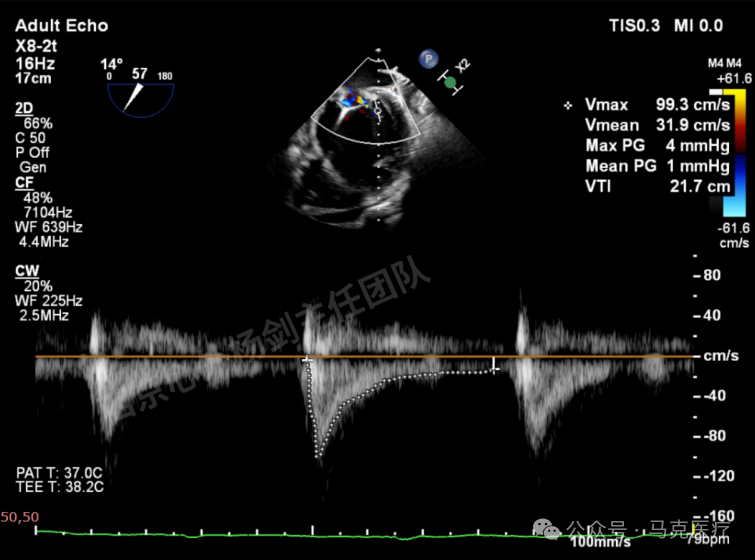

第二枚XT关闭后评估,trace

二尖瓣平均跨瓣压差1mmHg